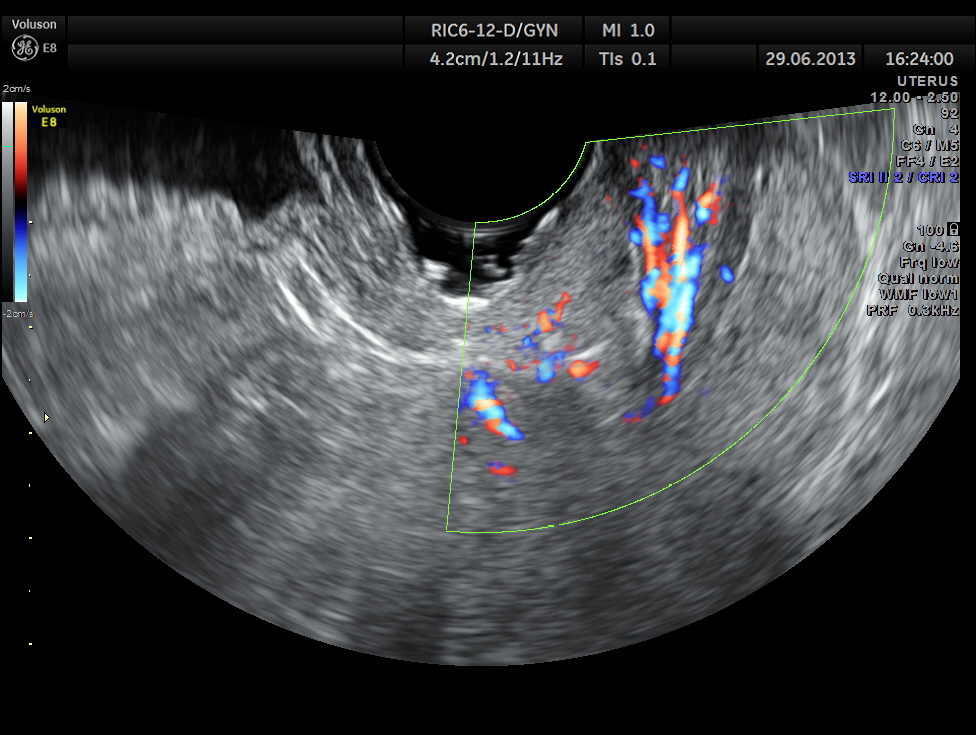

the following images are acquired trans vaginally and the starking difference in clarity can be appreciated.

the multi planar 3 d image shows increased flow in the polyp and the stalk arising from the endometrium

The diagnosis offered was an endometrial polyp with a long stalk situated in the cervix.

This case illustrates the superiority of trans vaginal scan over the trans abdominal mode ( though the diagnosis could have been made trans abdominally also.)